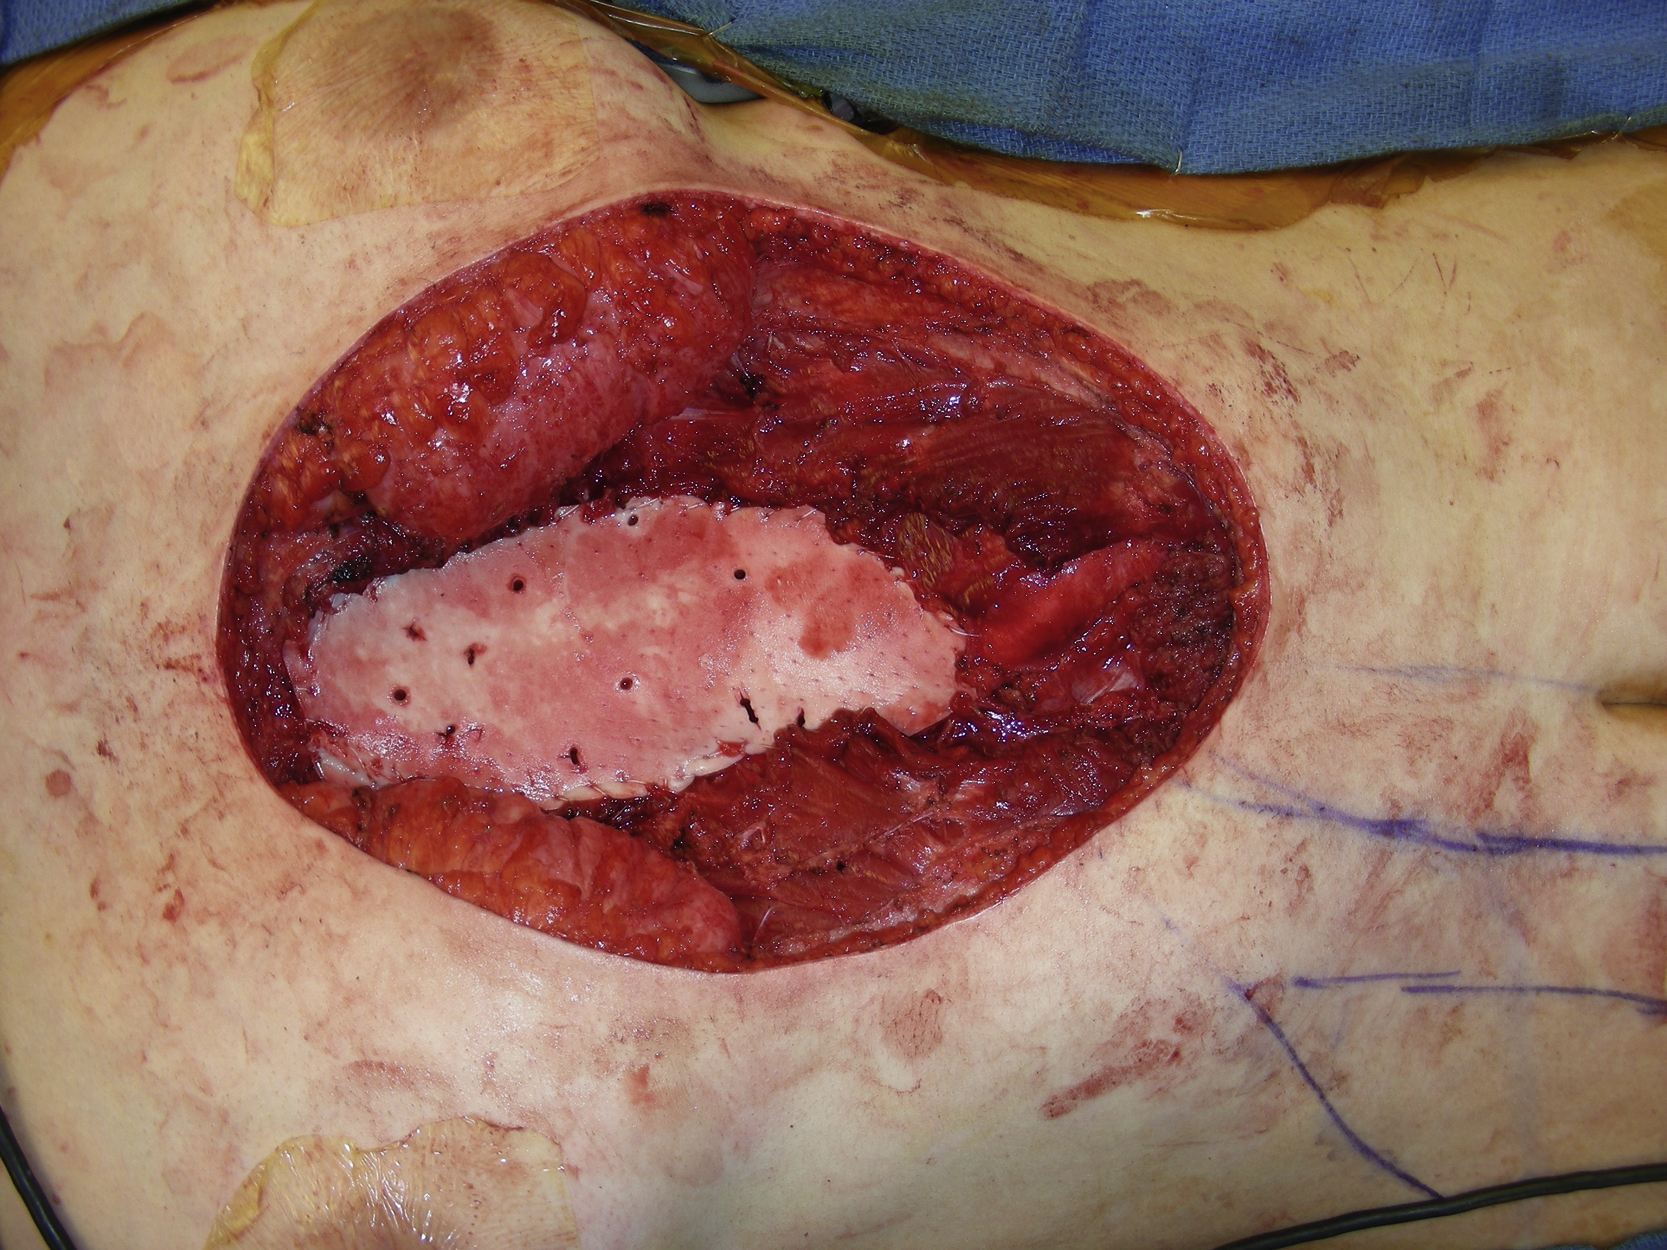

Under general anesthesia with the patient in the supine position, the reconstructive procedure started after an adequate tumor resection. A 5-cm posterior rectus sheath defect over the upper abdomen was repaired with 2-0 PDS sutures in a figure-of-eight. The lower sternal bony defect, measuring 13 × 6 cm, was reconstructed with Strattice. The selected Strattice had several perforated holes. Scissors were used to prepare a 13 × 6 cm Strattice, which was placed onto the lower sternal bony defect while the dermal side was facing up, approximated with several interrupted 2-0 PDS sutures followed by 2-0 PDS sutures in simple running fashion ( Fig. 23.3 ).

A right paramedian skin incision was designed in the right abdomen ( Fig. 23.4 ). The proposed incision was infiltrated with 1% lidocaine with 1:100,000 epinephrine. The procedure was started by making a paramedian incision to the anterior rectus sheath. Once the anterior rectus sheath was opened, the dissection was performed around the rectus abdominis muscle. During dissection, several tendious intersections were dissected free. The rectus abdominis muscle was identified and after further dissection around the muscle, its entire length was dissected free. The right inferior epigastric vessels were identified and divided with hemoclips near the muscle’s origin. The muscle was then divided with electrocautery very close to the suprapubic symphysis area and the muscle flap was completely dissected free from the posterior rectus sheath. Before further dissection of the muscle, the superior epigastric vessels were identified. The flap was then turned over to cover the soft tissue defect in the lower sternal area ( Fig. 23.5 ). The muscle flap was completely inset into the defect to cover the entire exposed Strattice and was approximated to the adjacent tissue with several interrupted 3-0 Vicryl sutures ( Fig. 23.6 ).